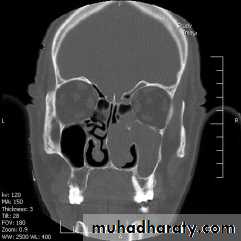

CT scan & MRI: show the tumor, bone erosion& extension of the tumor.

1- Radiology (opacity of the maxillary sinus and could extends to the ethmoid and nasal cavity and thinning of the bone but no frank erosion)